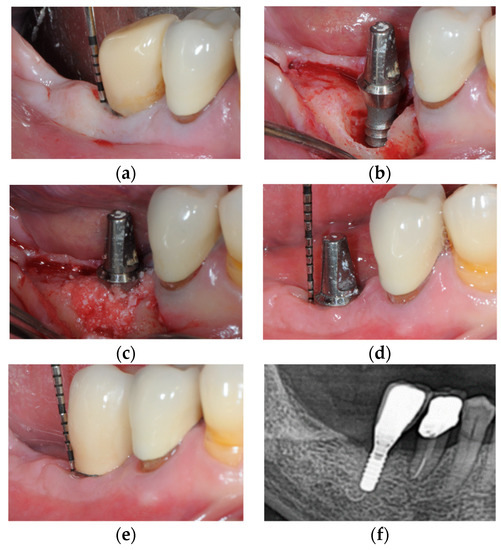

- Monje, A.; Pons, R.; Roccuzzo, A.; Salvi, G.E.; Nart, J. Reconstructive therapy for the management of peri-implantitis via submerged guided bone regeneration: A prospective case series. Clincal Implant Dent. Relat. Res. 2020, 22, 342–350. [Google Scholar] [CrossRef] [PubMed]

- Roccuzzo, M.; Dalmasso, P.; Pittoni, D.; Roccuzzo, A. Treatment of buccal soft tissue dehiscence around single implant: 5-year results from a prospective study. Clin. Oral Investig. 2019, 23, 1977–1983. [Google Scholar] [CrossRef] [PubMed]

- Monje, A.; Blasi, G.; Nart, J.; Urban, I.A.; Nevins, M.; Wang, H.L. Soft Tissue Conditioning for the Surgical Therapy of Peri-implantitis: A Prospective 12-Month Study. Int. J. Periodont. Restor. Dent. 2020, 6, 899–906. [Google Scholar] [CrossRef] [PubMed]